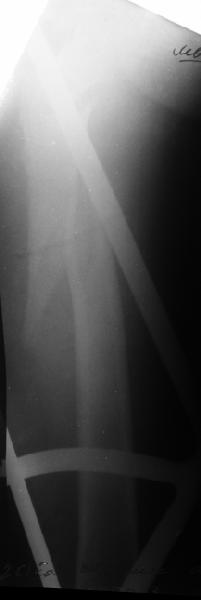

В диагноз пишем... Потом же как-то анализировать надо. Что-то никто не откликнулся на этот вопрос из англоязычных коллег. Все-таки - как такой перелом надо классифицировать? А если шейка бедра + диафиз? Завтра покажу такой случай.

Реконструкционный гвоздь.

Да, сейчас это и у нас самый напрашивающийся выбор. Сделали гвоздем ChM, картинки в приложении.